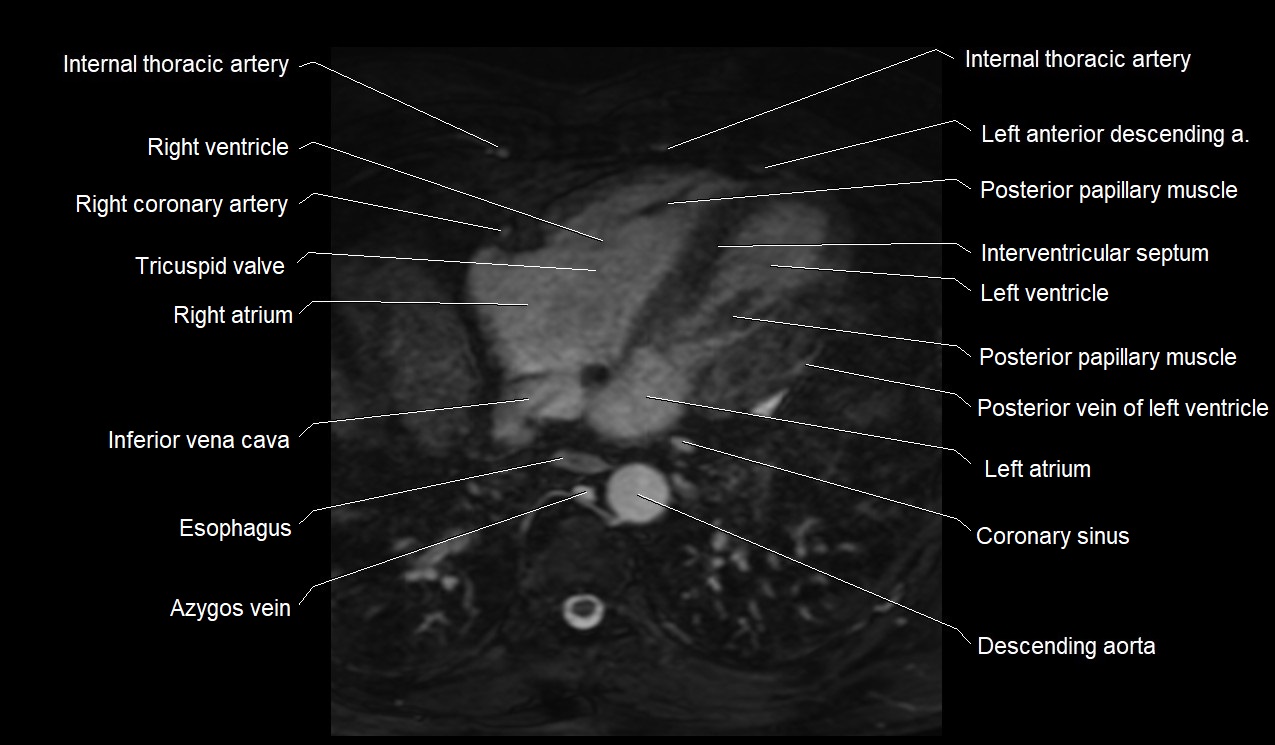

MRI image